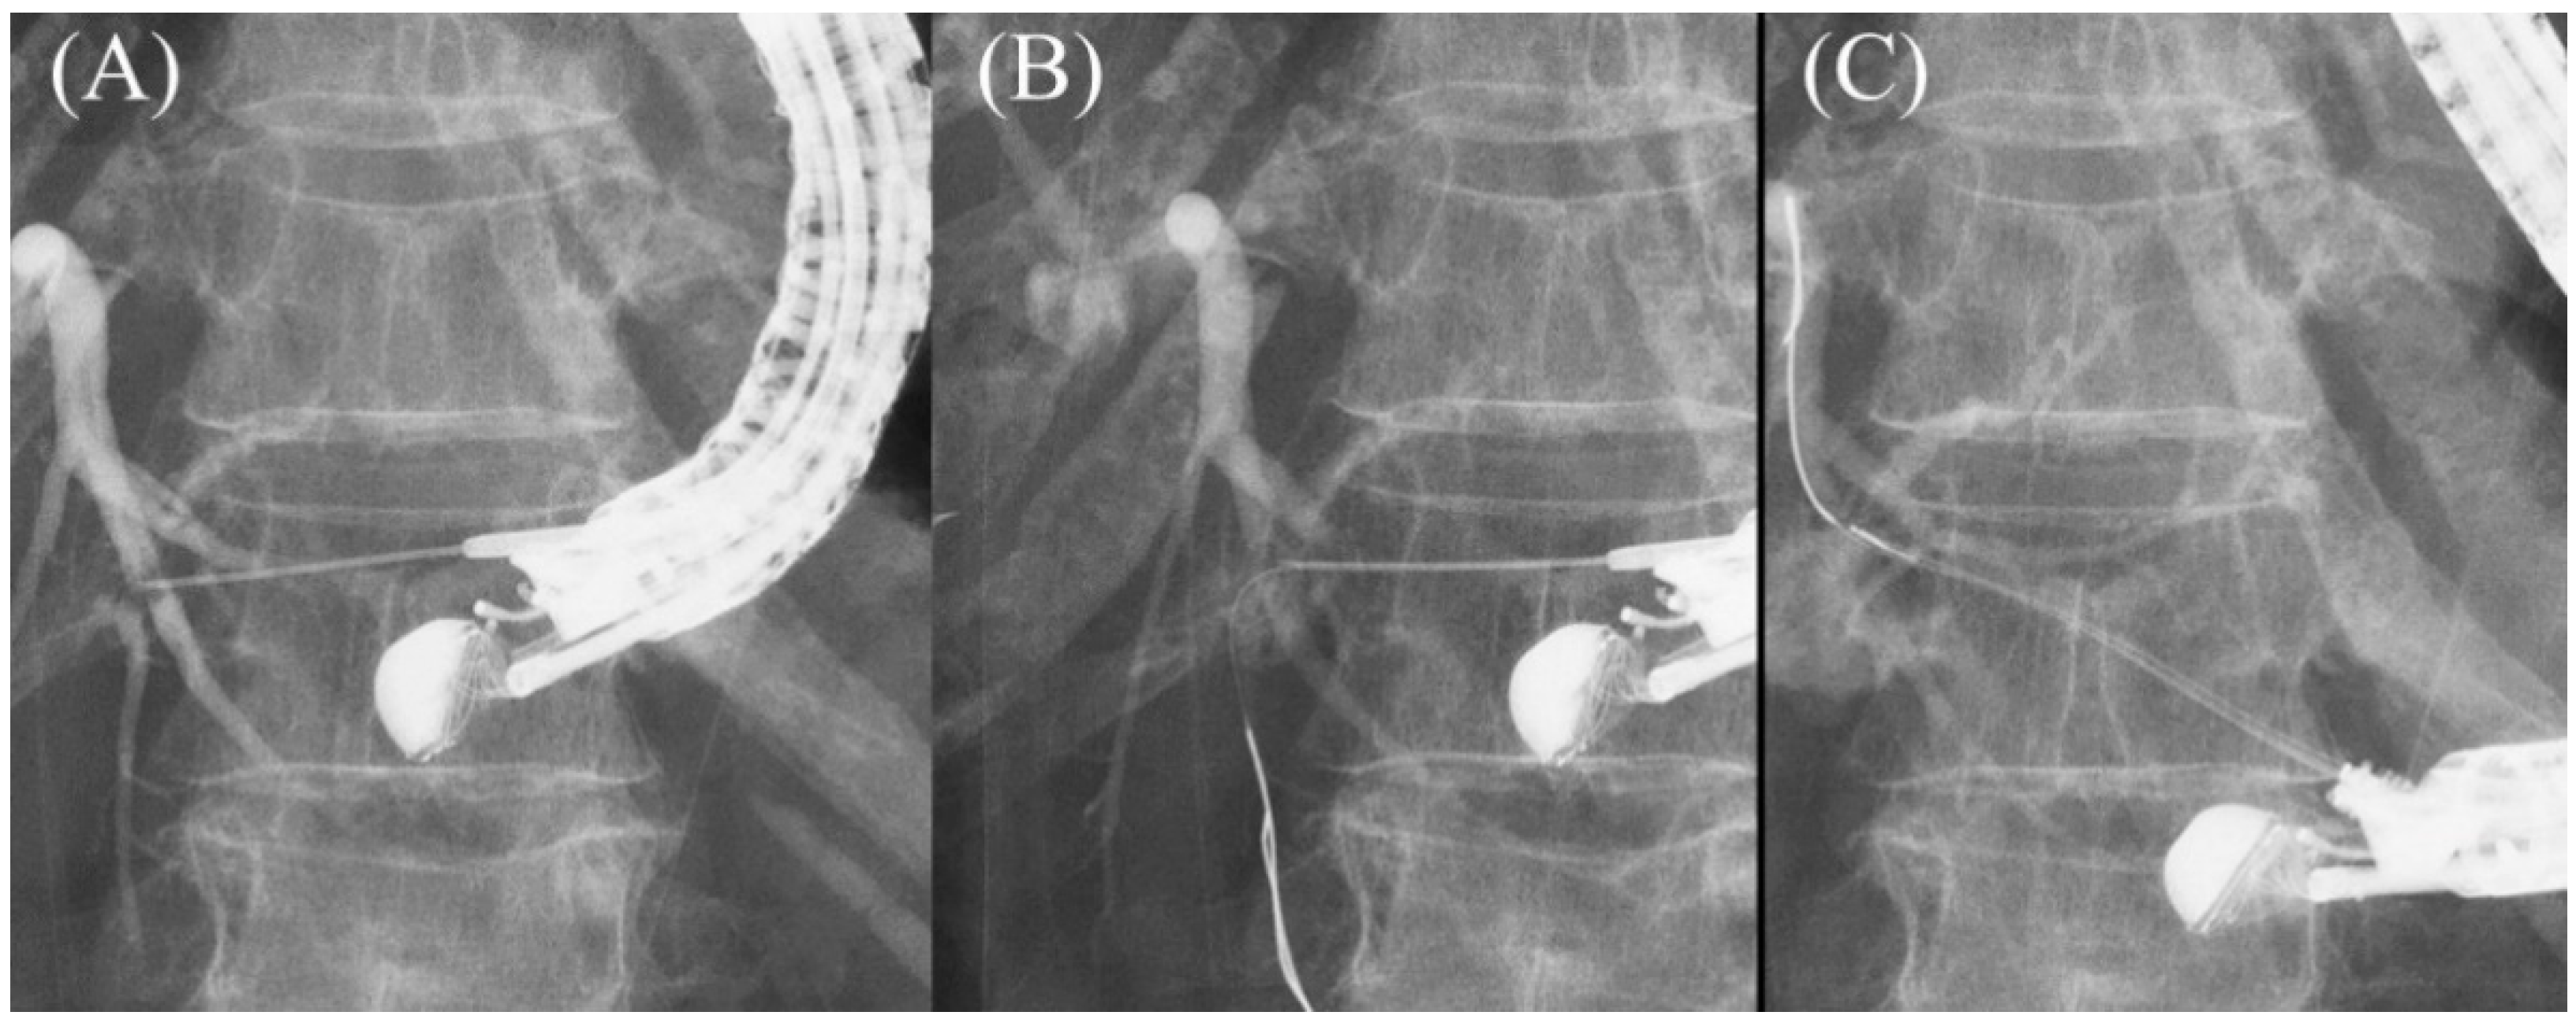

- Park, D.H.; Jeong, S.U.; Lee, B.U.; Lee, S.S.; Seo, D.W.; Lee, S.K.; Kim, M.H. Prospective evaluation of a treatment algorithm with enhanced guidewire manipulation protocol for EUS-guided biliary drainage after failed ERCP (with video). Gastrointest. Endosc. 2013, 78, 91–101. [Google Scholar] [CrossRef]